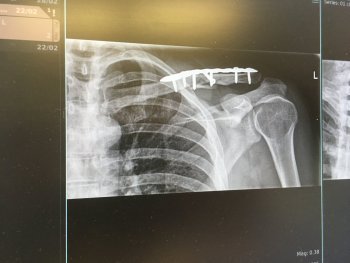

Although I've had that repaired:

IMG_0274.jpeg